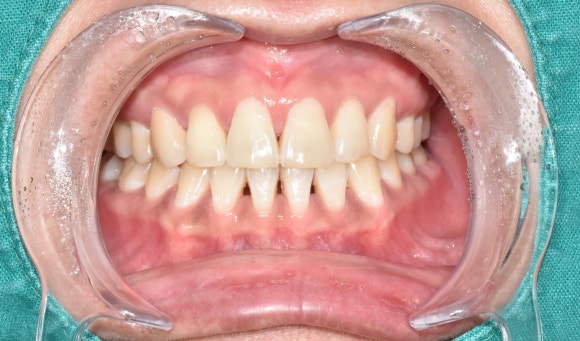

두번째 케이스

왼쪽에 보이는 작은 앞니에 주목해주세요.

이 경우도 마찬가지로 오랜기간 괴사를 겪으면서 짙은 오렌지색으로 변색된 케이스입니다.

마찬가지로 신경치료 후에 미백치료를 시작하였고, 3회차에 치료를 종료하셨습니다.

치료 전 후